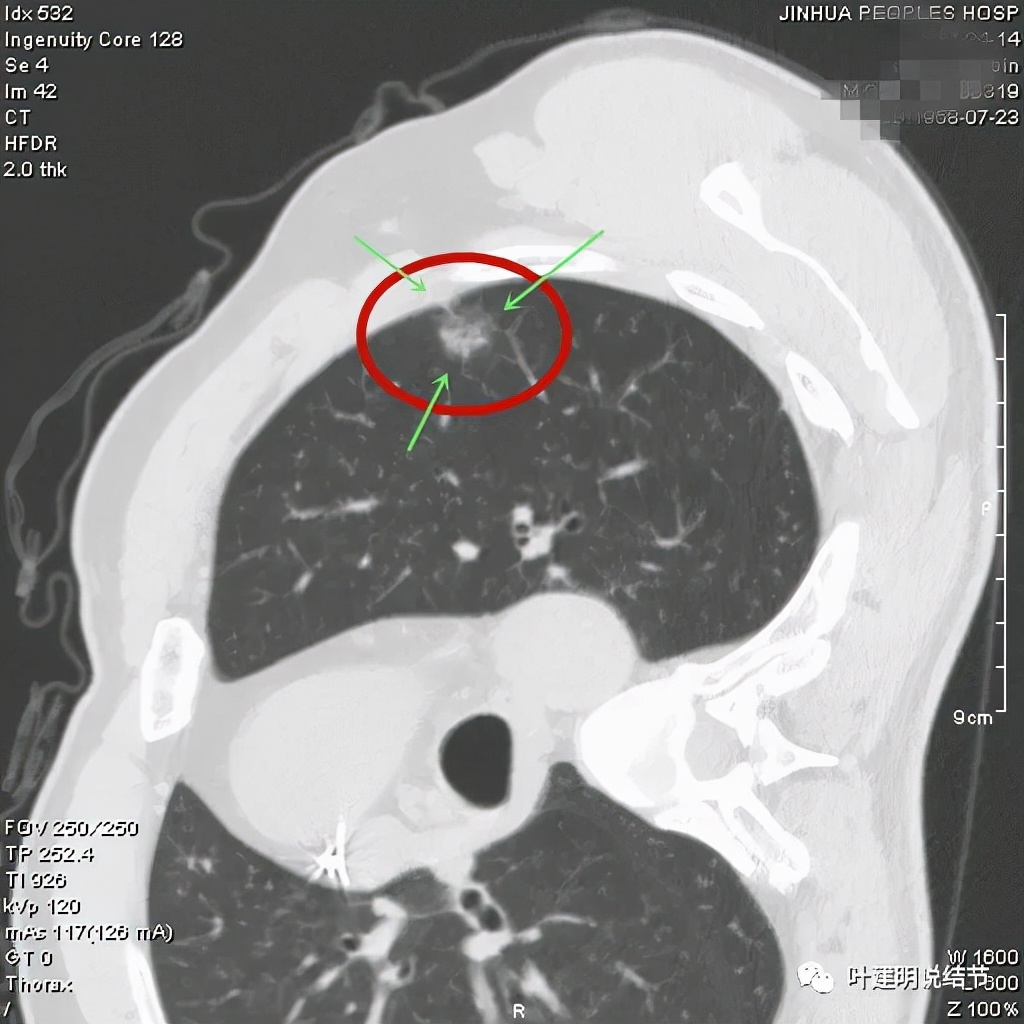

从以上靶扫描图像上看,给人的印象是肿瘤范畴的结节,是混合磨玻璃结节,但磨玻璃部分的密度偏低,有的边缘显模糊,中间有点状高密度,也有微小血管进入,应该至少微浸润性腺癌可能性大。持续存在已经2月余,位置又还靠边上的,可考虑手术切除。下面再来瞧瞧后处理重建的图像:

上图非常不舒服,病灶边缘有毛刺(蓝色箭头),中间有偏实性成分(粉色箭头所指),整体看密度不均杂乱

上图示明显的血管进入(桔色箭头),而且进入病灶后散大模糊,不是穿行;病灶内有高密度区域(粉色箭头)。但事后分析,绿色箭头所指的磨玻璃部分密度仍是过低,且边缘显模糊,与浸润性腺癌可能不是太符合。

以上三图均示典型的混合磨玻璃,实性成分杂乱,整体密度杂乱,并有血管征,是较为典型的浸润性腺癌影像表现。